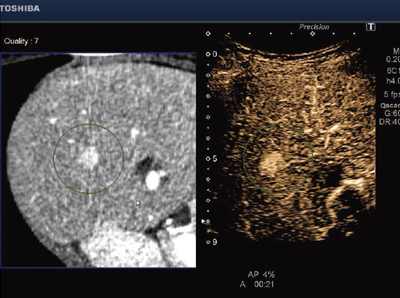

Realtime Application Platformとは,高速リアルタイム処理を実現し,新アプリケーションを可能とするプラットフォームである。elastographyをはじめ,びまん性肝疾患の評価に期待される当社独自のASQ(acoustic structure quantification)をリアルタイム化。また,エコー像とCT画像を連動させ,病変の検出および治療支援に有効なSmart Fusionにも新たに対応している(図3)。これらの機能により,病変の検出および質的診断に期待が持たれる。

図3 同じ病変部位をCTと超音波の両方から観察するSmart Fusion